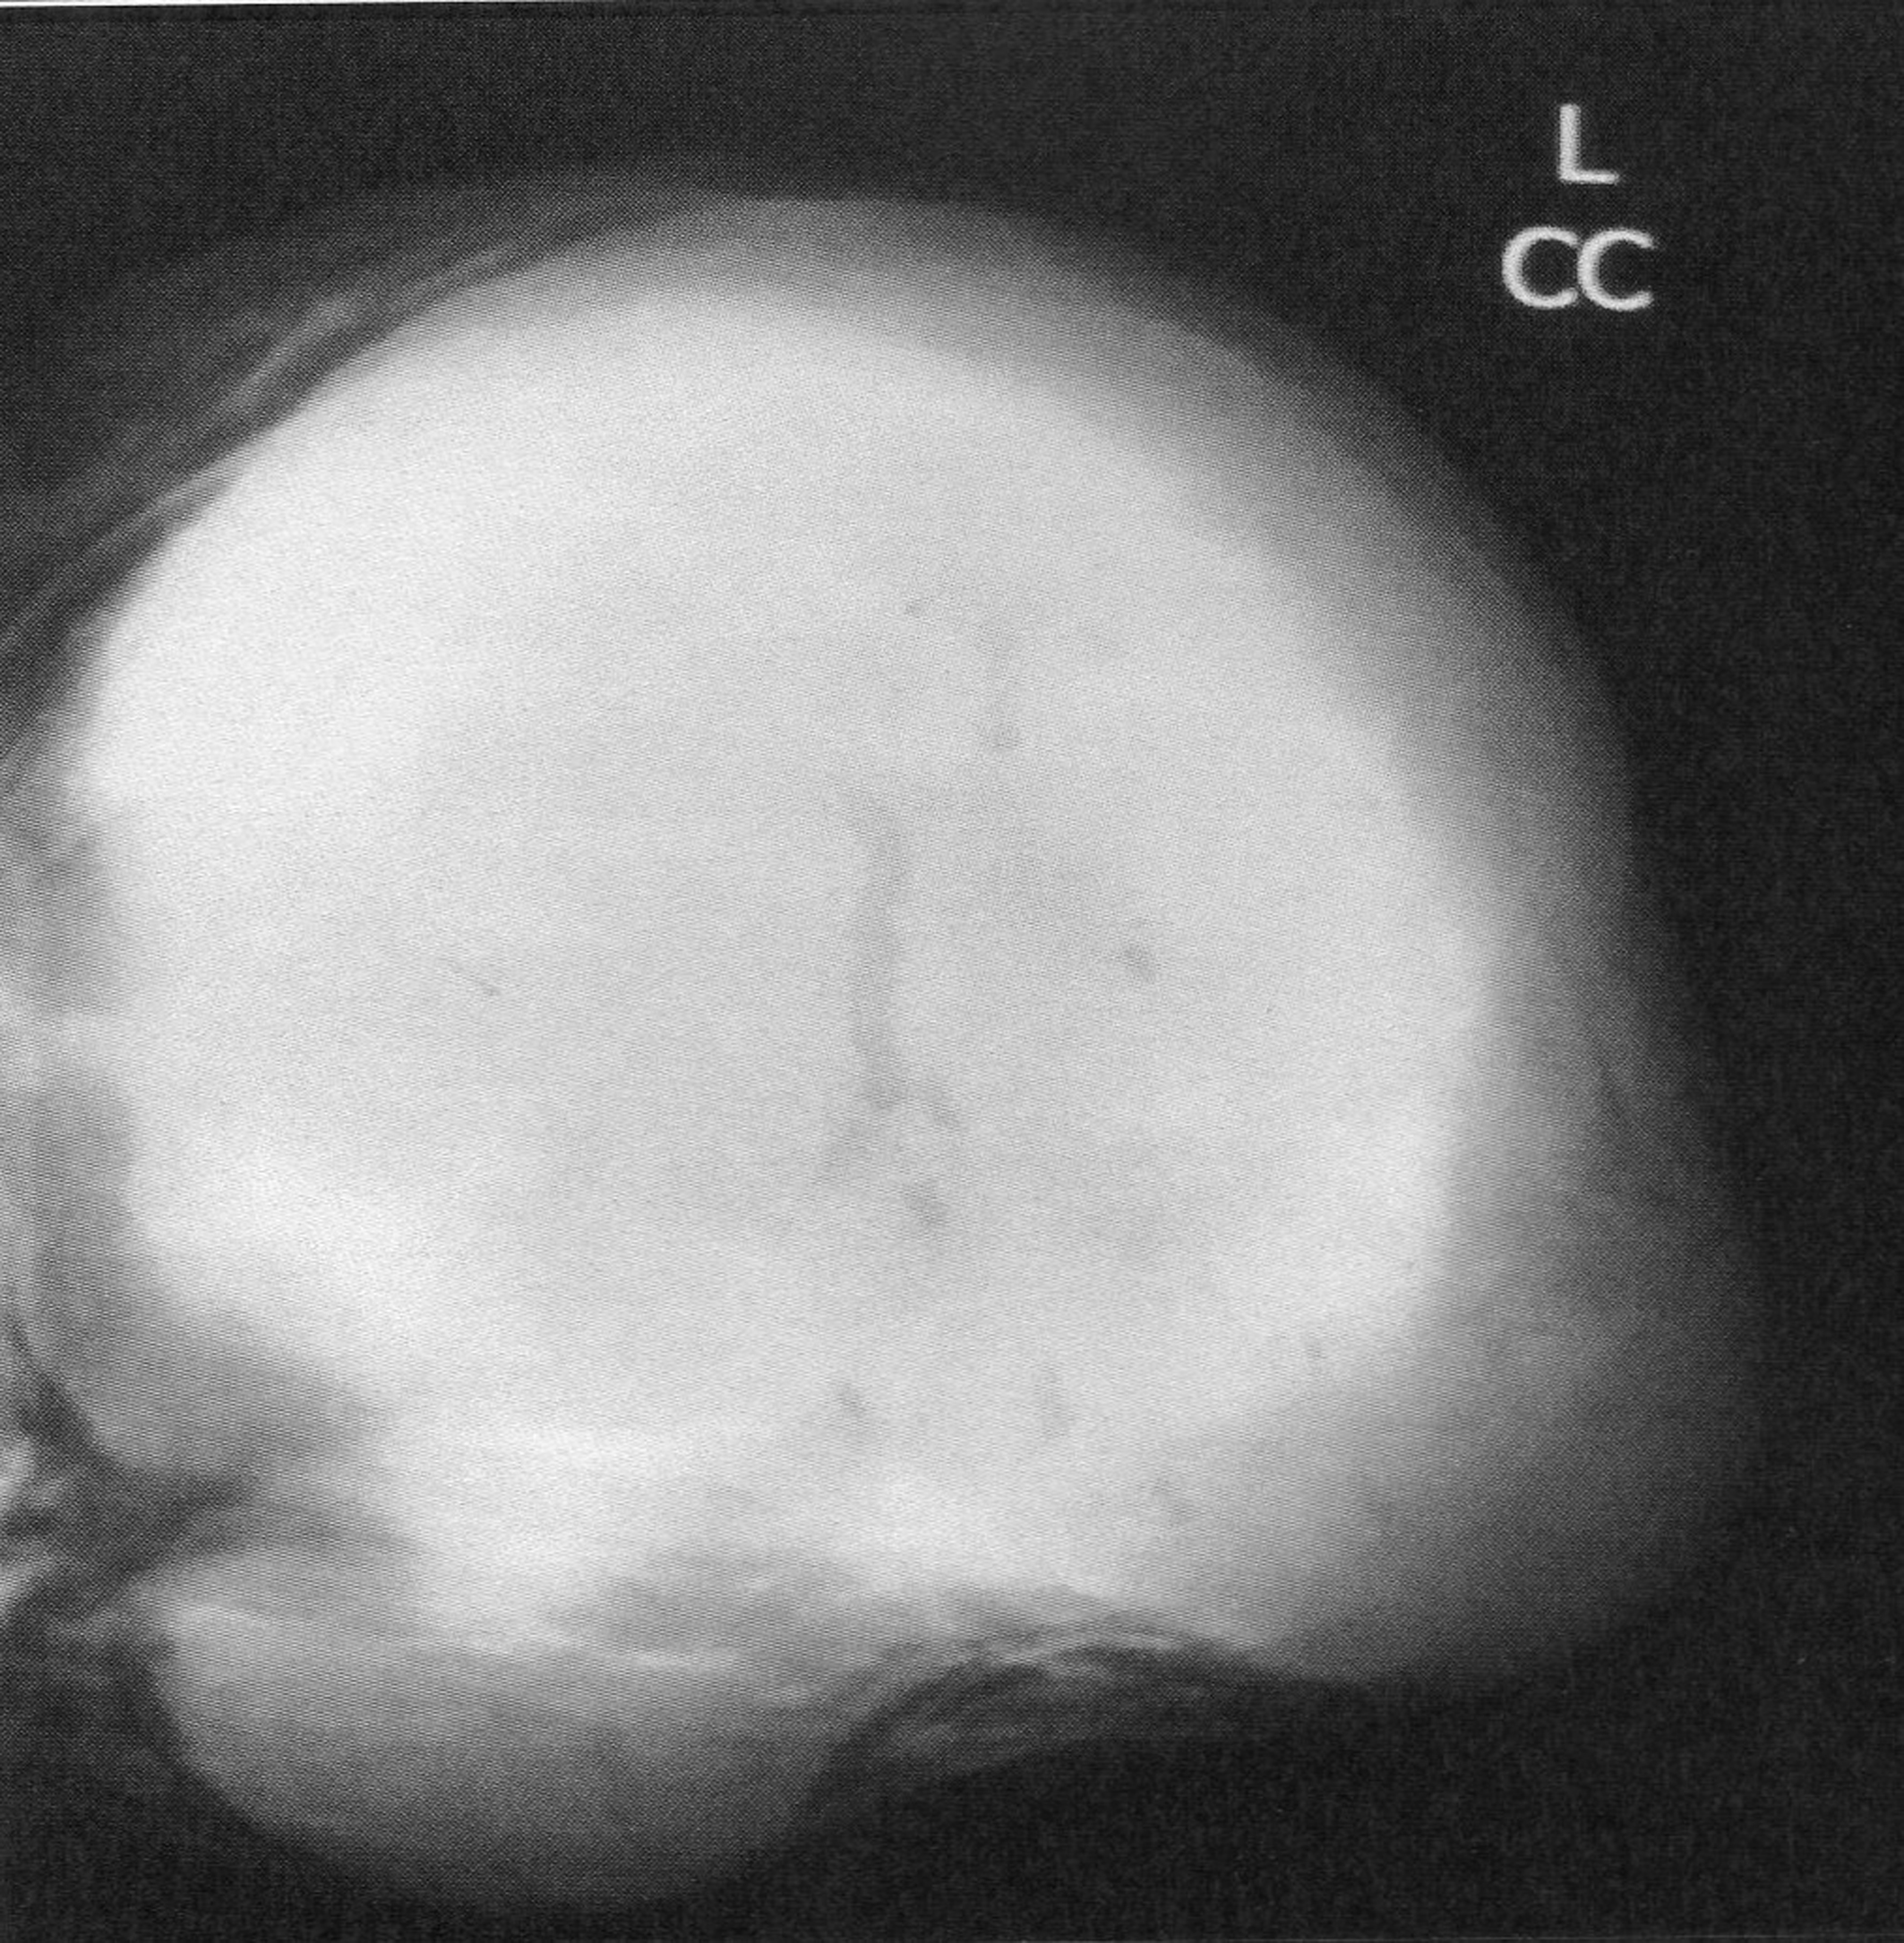

The mean time from onset of symptomatology and pathological diagnosis of PT ranged from 1 to 96 months (mean 20 months). The tumors occurred in the left breast in 12 cases, in the right one in 13 cases and in the remaining case, it was bilateral. The upper outer quadrant was involved in 11 cases (42.3%). Mammography was made in 25 cases and showed a well defined opacity (Fig. 1) in 14 cases, suggesting the diagnosis of PT in 8 cases. In 11 cases, mammography showed a poorly circumscribed mass suggestive of malignancy. Echography, performed in all the cases, showed a heterogeneous, hypoechoic, well delineated, and cystic mass (Fig. 2) suggesting a PT in 16 cases. In 4 cases, the diagnosis of fibroadenoma was suggested and in 6 cases, it was doubtful between PT and fibroadenoma. Fine needle aspiration was performed in 4 cases and suggested the diagnosis of PT in only one case.

![]() Click for large image | Figure 1. Mammography revealing a lobulated mass with smooth margins. |

Mammography and ultrasound appearances are non-specific and the pre-operative diagnosis of PT is difficult since rapid growth and/or large size of apparent fibroadenomas may be the only imaging findings suggesting PT [10]. PTs appear on mammography as lobulated round or oval masses with well-circumscribed borders and rarely contain calcifications [11-13]. On sonography, PTs are usually well-defined, solid masses with heterogeneous internal echoes, without posterior acoustic attenuation. A diagnosis of PT should be considered if sonography reveals fluid-filled, elongated spaces or clefts in a solid mass. It is often difficult to differentiate PT from fibroadenoma on sonography or mammography, and it is not possible to distinguish between benign and malignant PTs on the basis of sonographic or mammographic findings [9]. Magnetic Resonance Imaging may be used to delineate the full tumor extent and potential satellite lesions before surgical excision [13]. PTs can occur synchronously with fibroadenoma with an incidence higher than the percentage seen in the general population [7]. The percentage of concurrent fibroadenomas varies from 4.2% [14] to nearly one third of women with PTs [10].